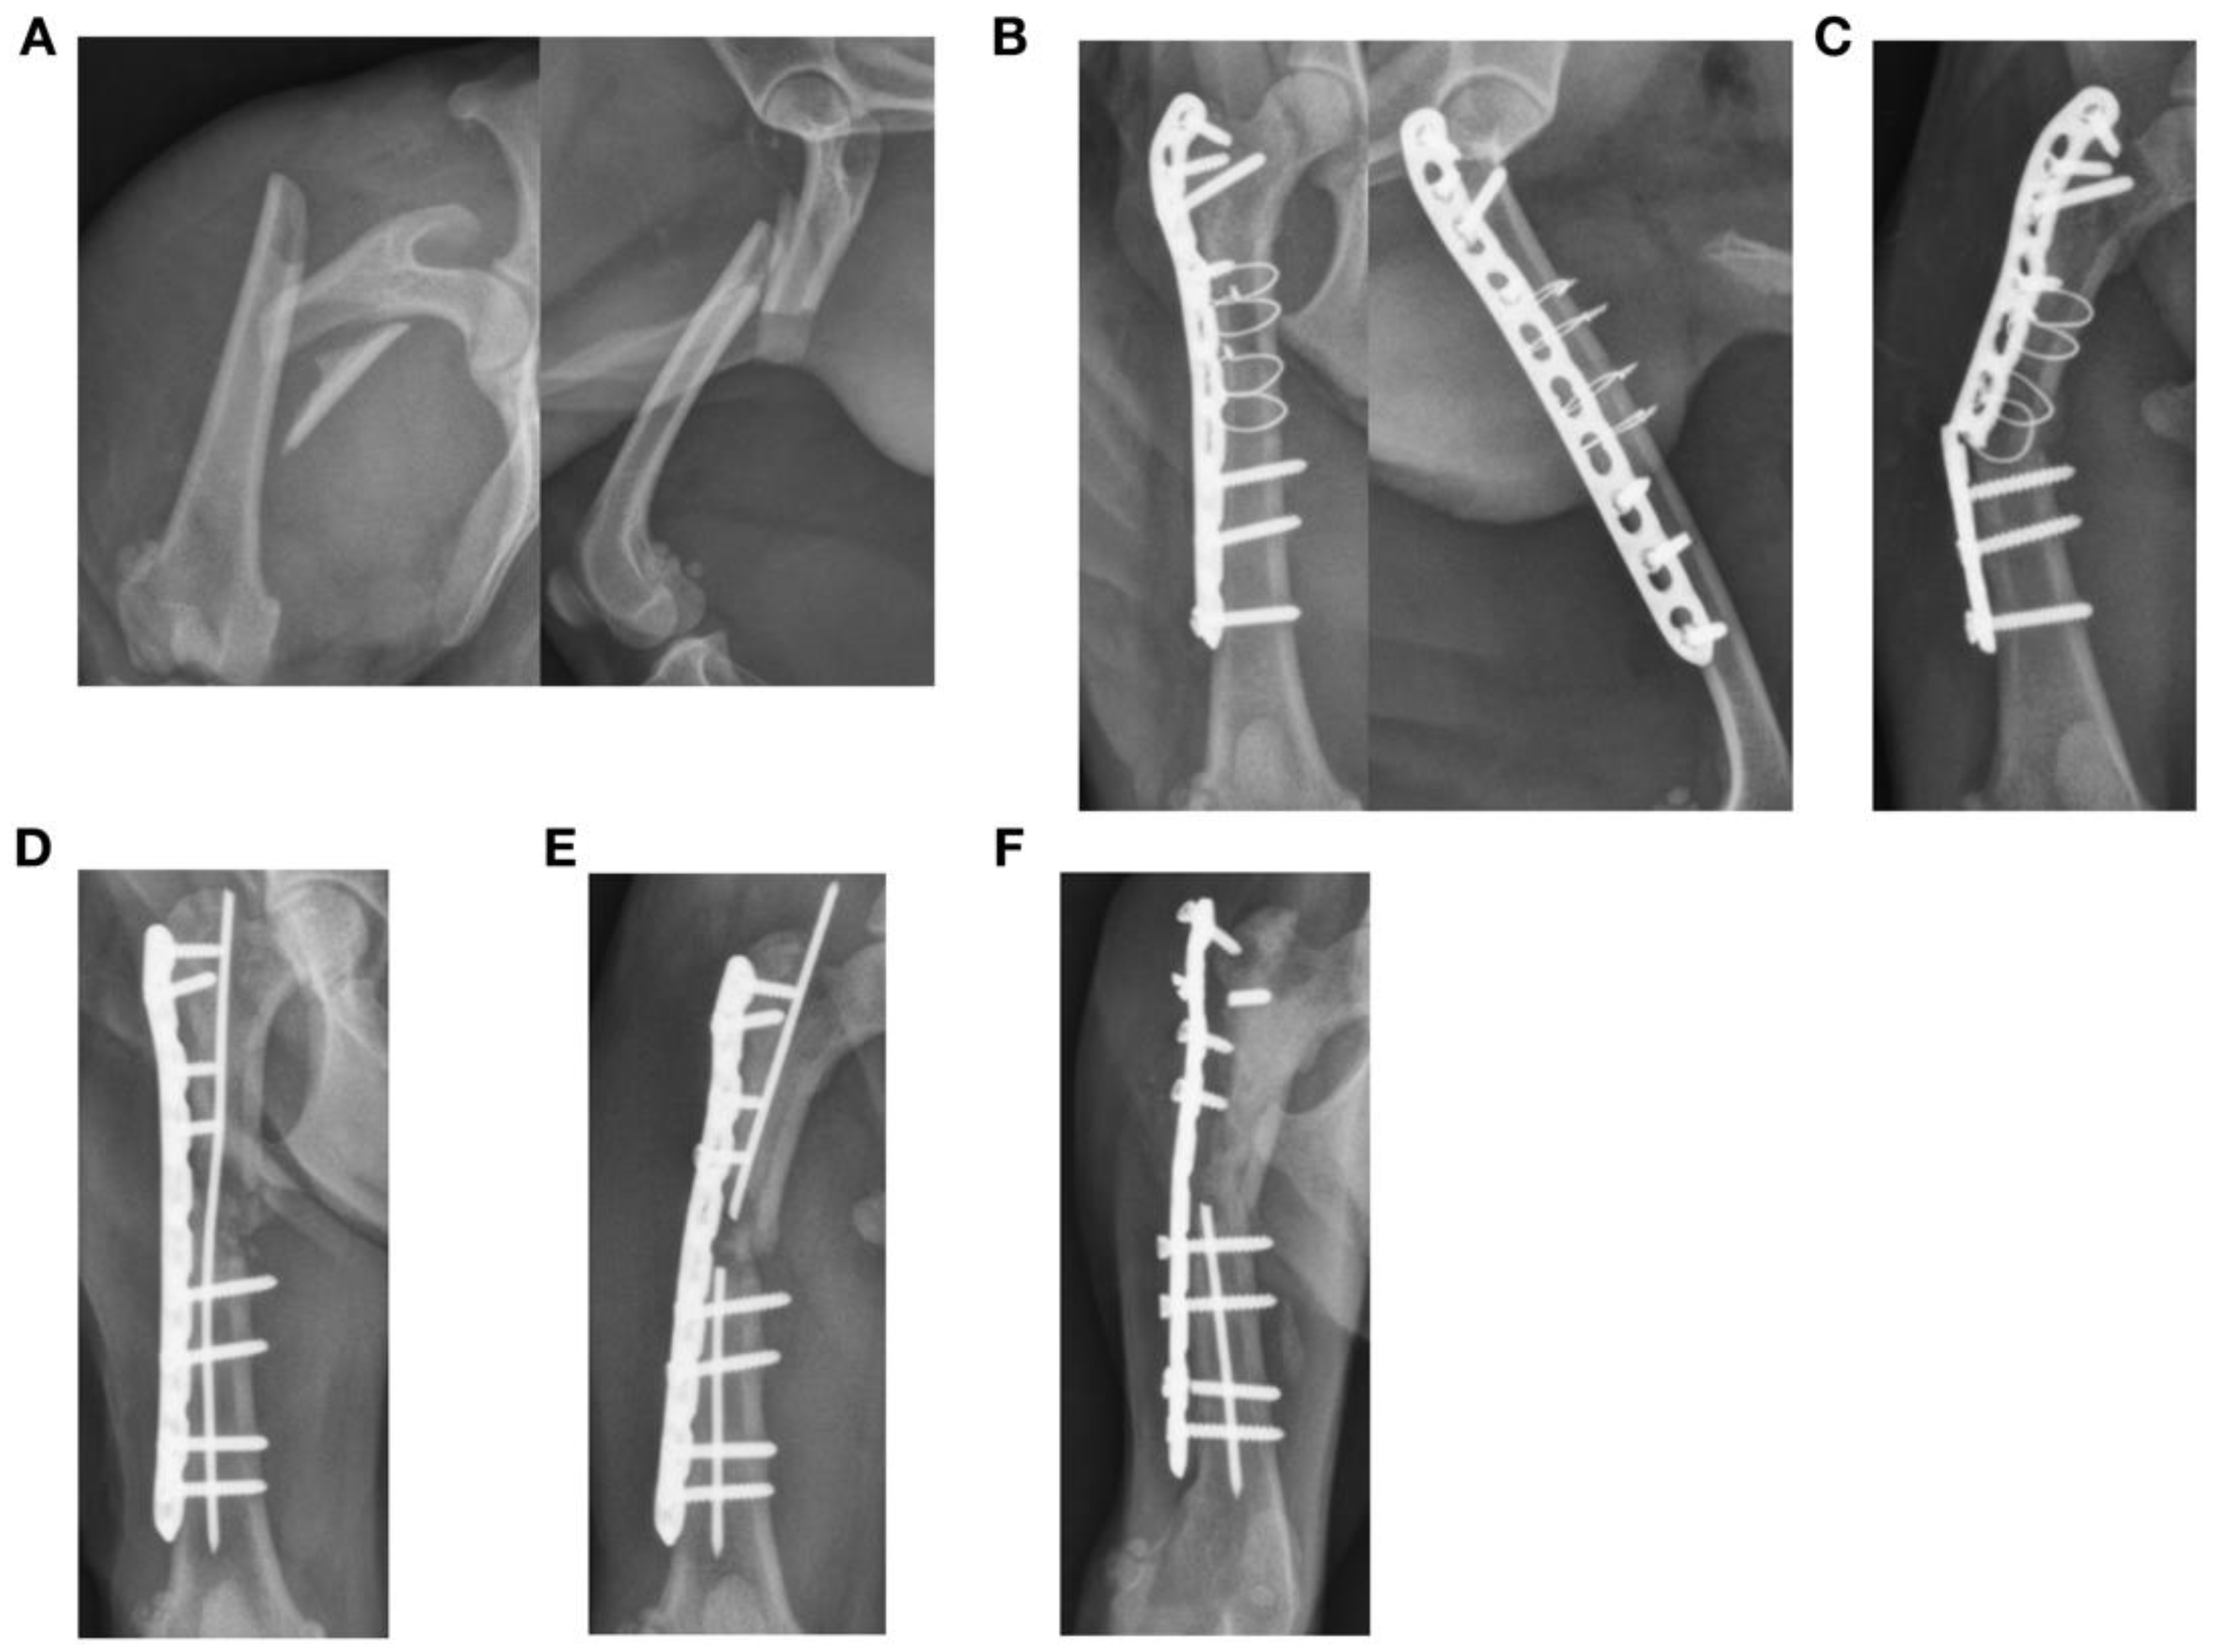

Figure 5.

Failure of a bridging plate construct used to treat a closed comminuted left femur fracture in a seven-year-old male intact shih tzu cross. (A,B) The fracture was stabilized with a 10-hole 1.5/2.0 mm LCP with seven 2.0 mm screws and four loops of 24-gauge cerclage without use of bone grafting. Five cortices engaged the proximal bone segment, and six cortices engaged the distal segment. Three plate holes over the area of comminution were left unfilled. Plate span was 70%. (C) Plate breakage at the level of the fracture was identified at 14 weeks. (D) The fracture construct was revised with an 0.045″ intramedullary pin and a replacement plate with two empty holes over the fracture. Cancellous bone autograft and omentum were placed in the fracture site. (E) Failure of the revised construct was found at 6 weeks. The broken pin was removed, bone morphogenic protein was placed in the fracture site and a Spica splint was applied. (F) Further failure of the construct with breakage and loosening of the proximal screws was found at 30 weeks with quadriceps contracture and palpable instability at the fracture site. Amputation was performed at 323 days after treatment started because of nonunion.